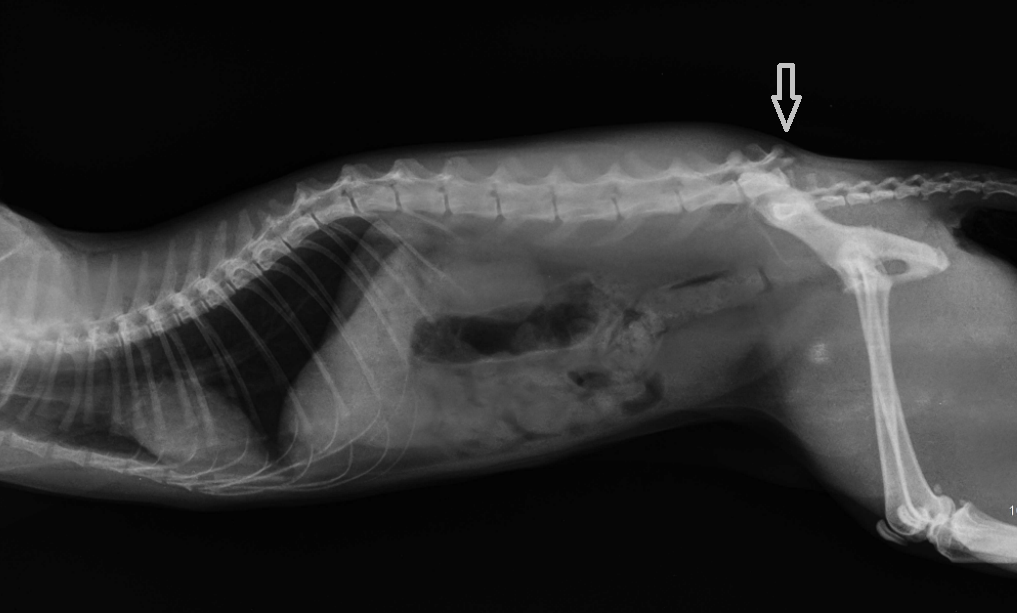

Заболевания позвоночника у домашних животных: диагностика и лечение

Раздел: Визуальные истории